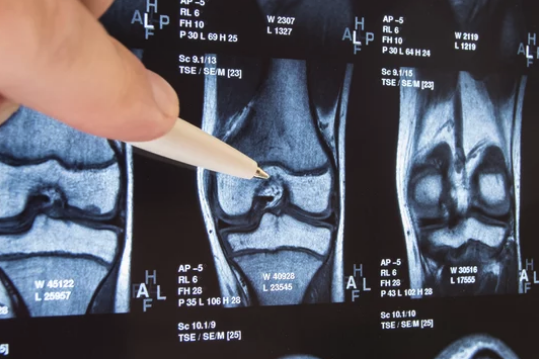

Lesiones de Meniscos en Rodilla

Los meniscos cumplen varias funciones importantes en la rodilla. Ayudan a absorber los impactos y a distribuir la carga entre los huesos de la articulación, lo que reduce la fricción y el desgaste del cartílago articular. Además, contribuyen a la estabilidad de la rodilla al mejorar la congruencia entre la superficie de la tibia y el fémur. Sin embargo, los meniscos son susceptibles a sufrir lesiones, especialmente durante actividades deportivas que implican giros bruscos o movimientos de torsión de la rodilla. Las lesiones meniscales son comunes y pueden variar en gravedad, desde pequeñas rupturas hasta desgarros completos. Los síntomas de una lesión meniscal pueden incluir dolor en la rodilla, hinchazón, sensación de bloqueo o atrapamiento en la articulación, disminución de la movilidad y sensibilidad en la línea articular. El diagnóstico de una lesión meniscal generalmente se realiza mediante la evaluación clínica, pruebas de imagen como resonancia magnética y, en algunos casos, artroscopia, que es un procedimiento quirúrgico que permite visualizar y tratar los problemas en el interior de la rodilla.